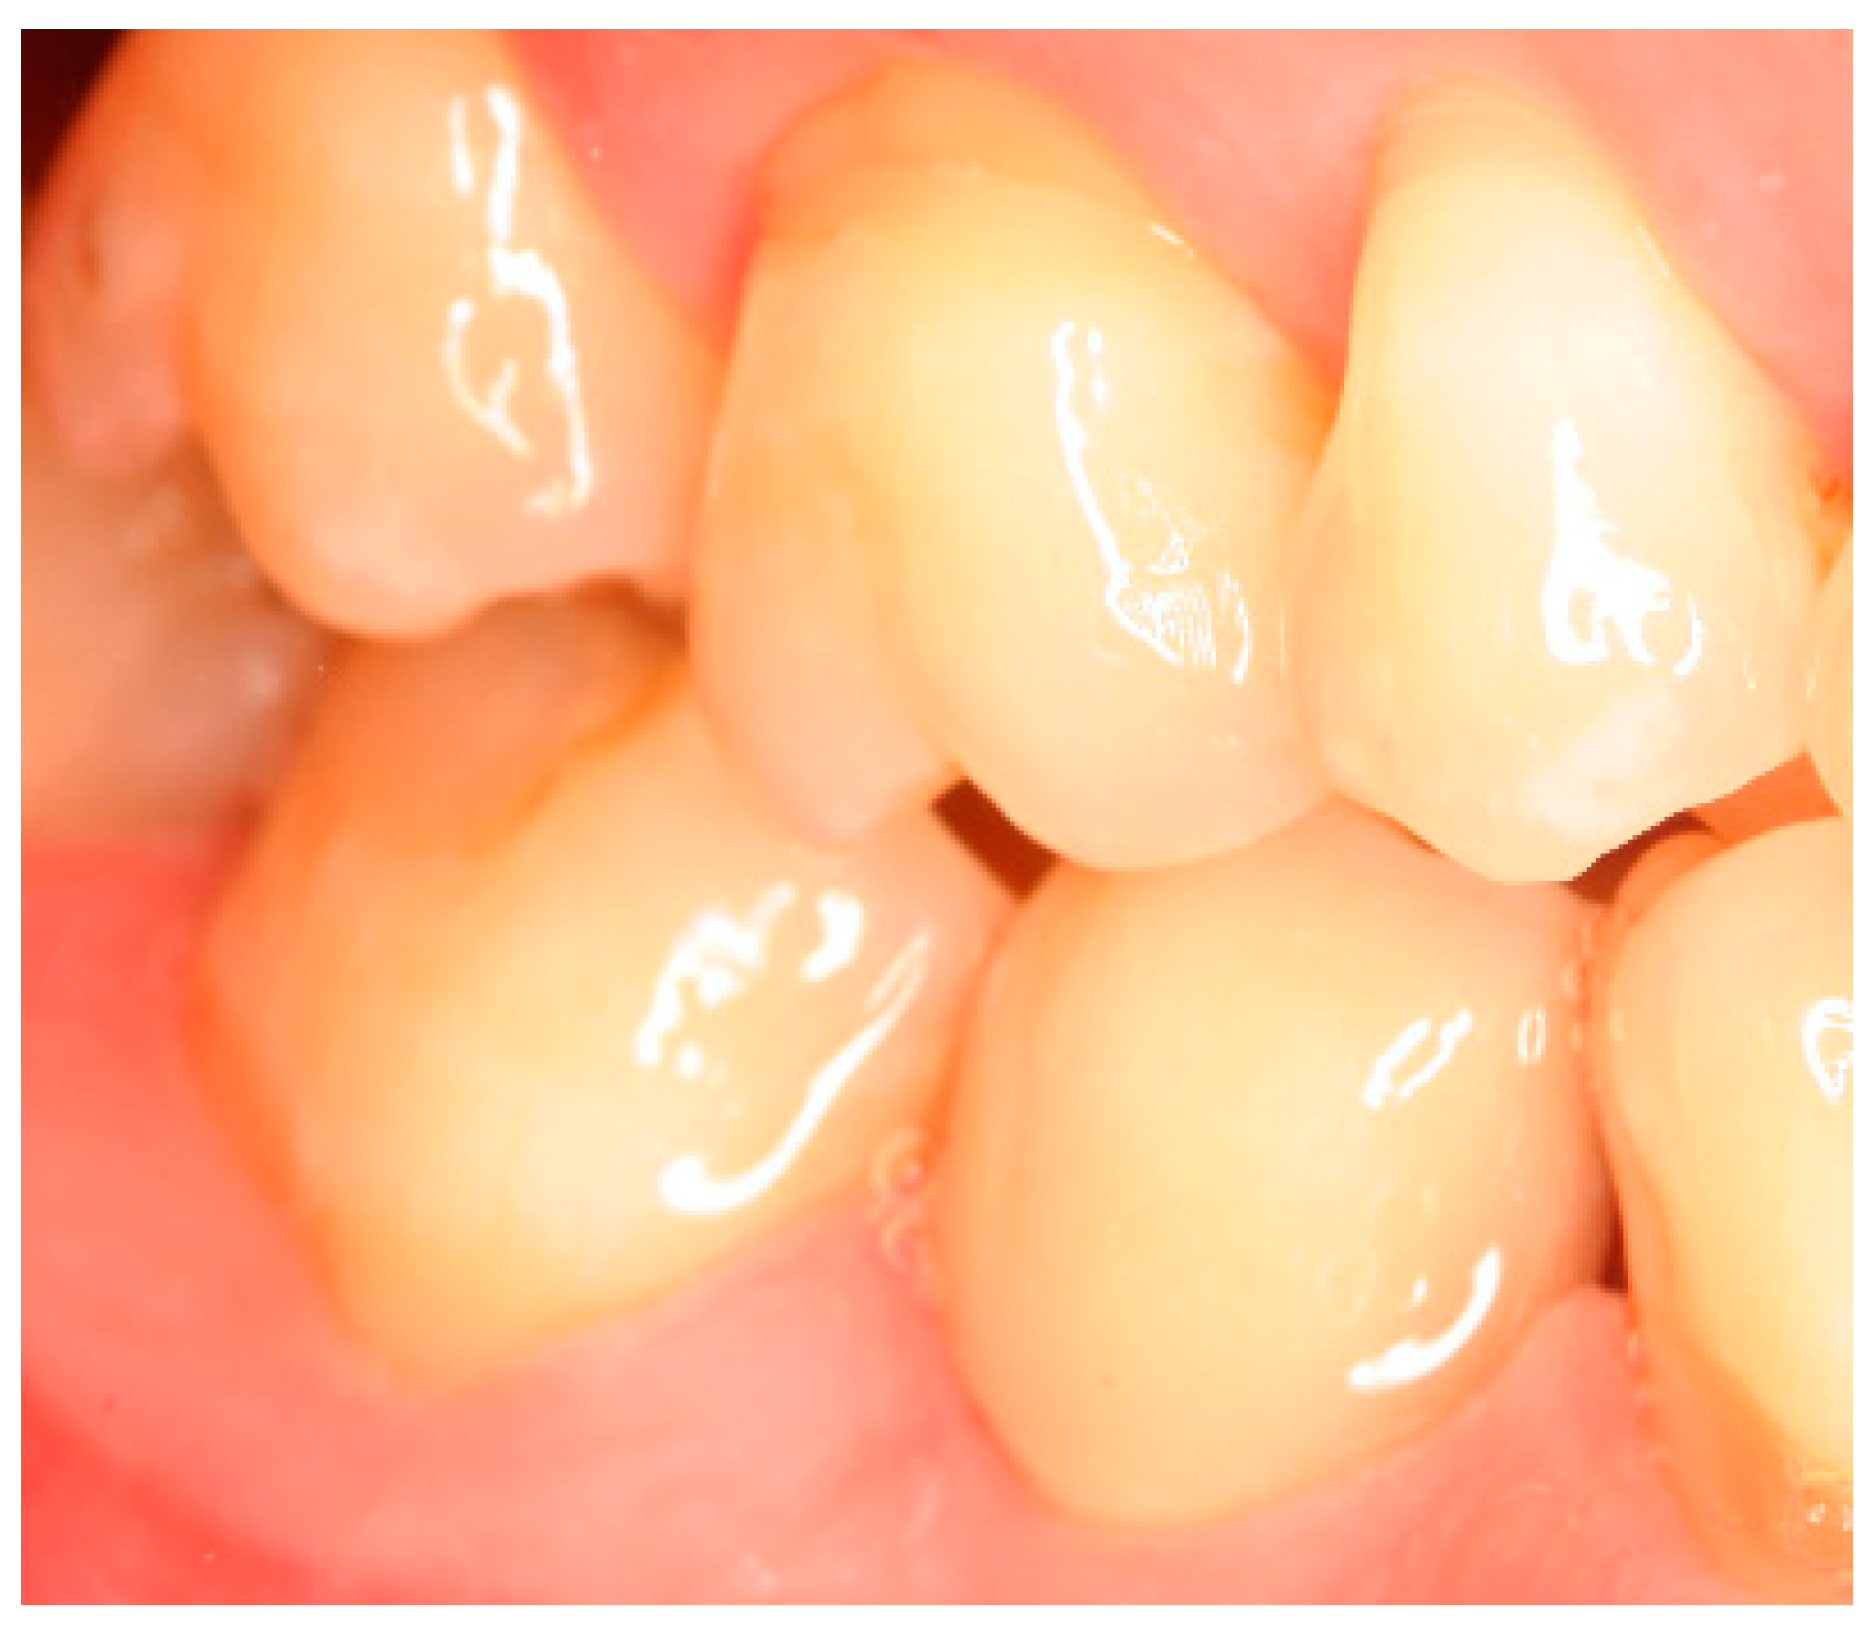

Appendix B. Exemplary Photographs and Radiographs from a Patient at Different Examination Time Points and a More Negative Outcome